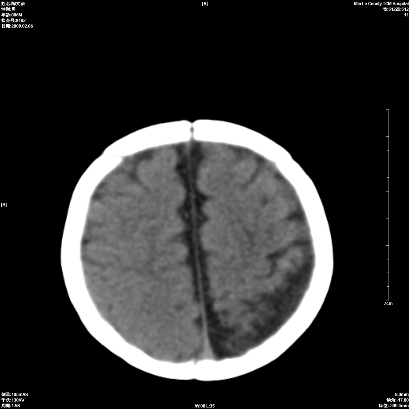

以下是引用wxq2008在2009-2-6 17:01:00的发言:[br]hie后遗症脑萎缩。

以下是引用学医在2009-2-6 21:45:00的发言:[br]hie后遗改变